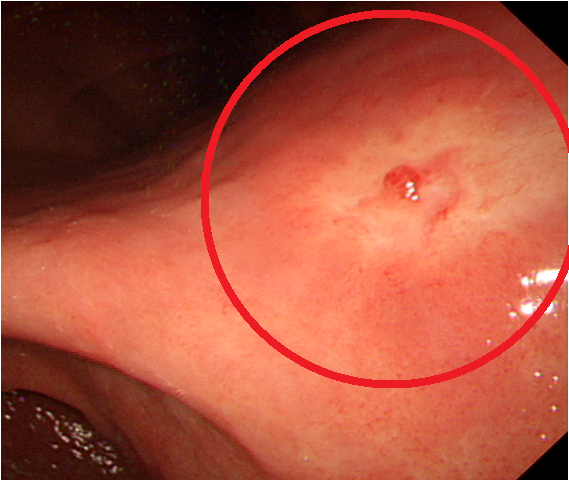

- 위암 초기증상 : 위축성 위염

위축성 위염이 있으면 위암에 걸릴 확률이 6배 더 높다고 합니다. 또는 이미 위축성 위염이 발생했다면 위가 다시 정상적으로서 회복되지 않을 수 있어요. 따라서 일정 기간 동안 내시경 검사를 통해 후속 조치를 취하는 것이 필요합니다. 짠 식품을 피하는 것도 매우 필요합니다. 위축성 위염은 위산 분비가 눈에 띄게 떨어뜨리여 소화 행동이 저하돼요. 또는 위암으로써 이어지는 것은 위 점막 세포의 변형이라고 해요.